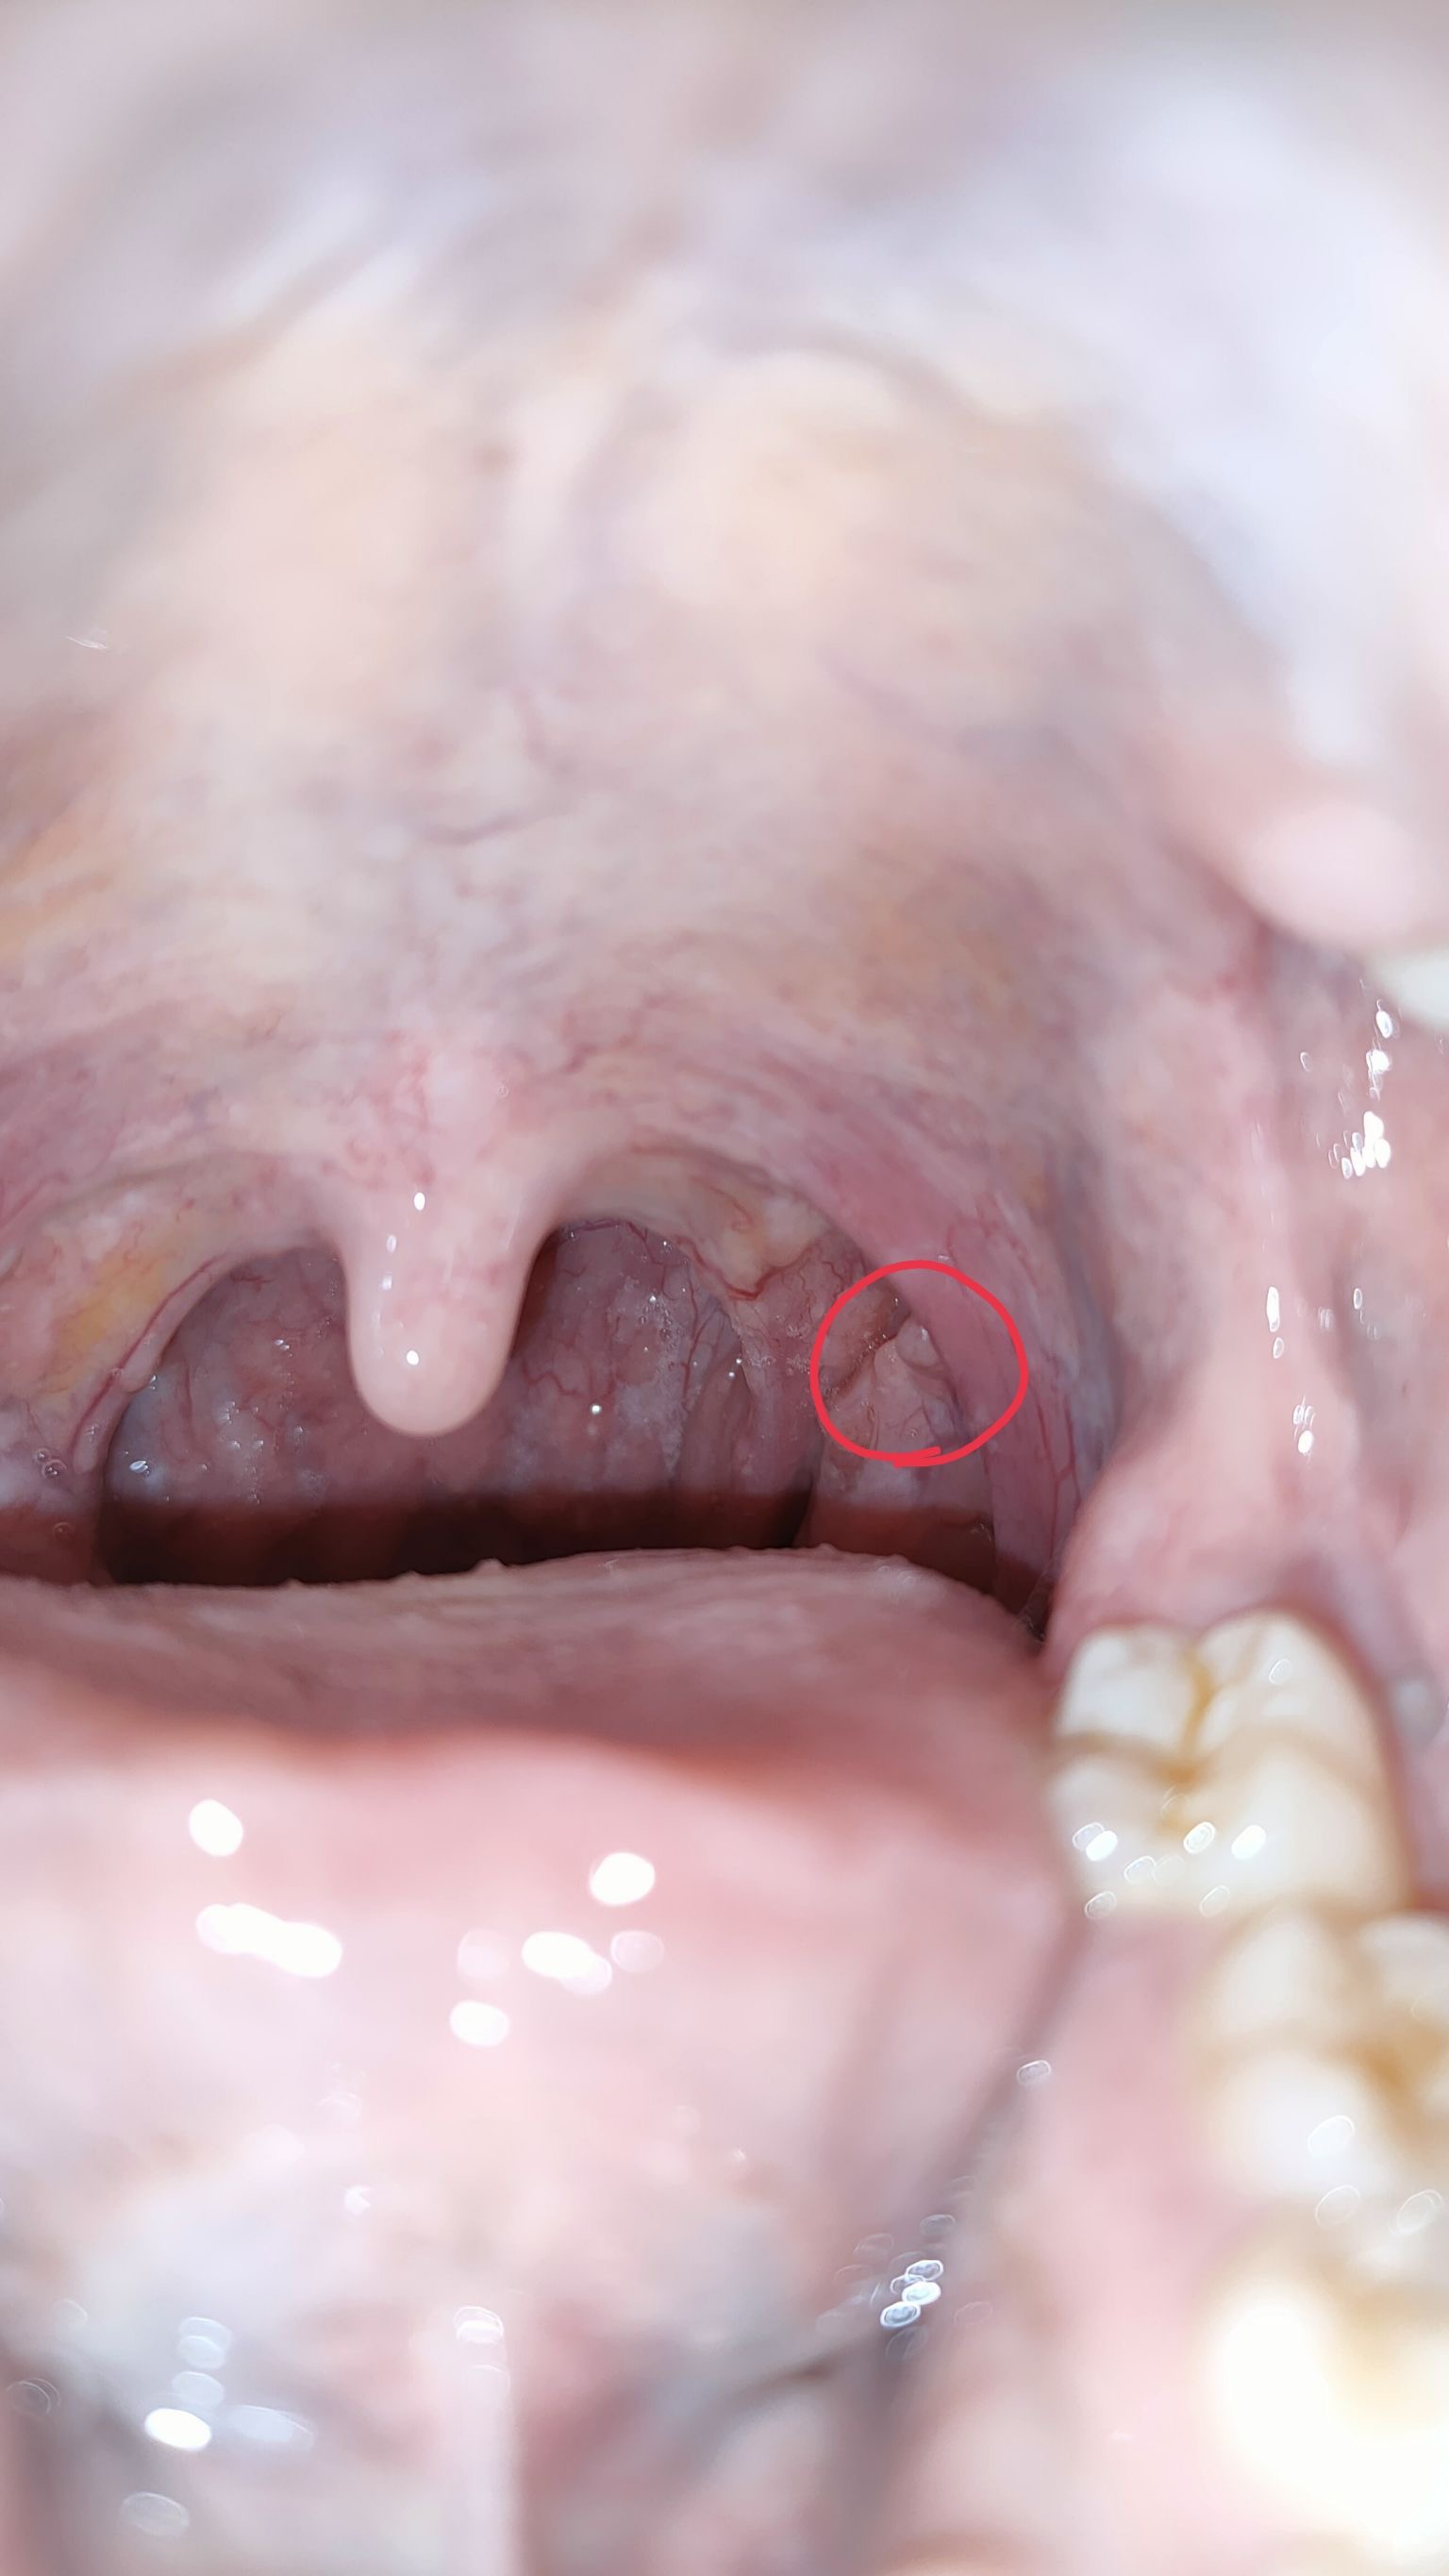

16 พฤษภาคม 2568 12:57:25 #1 https://haamor.com/media/create_topic/20250516125041.jpeg https://haamor.com/media/create_topic/20250516125040.jpeg อันนี้ผมพยายามอ้าให้เห็นสุดๆ แล้วครับ บางครั้งมองผ่านๆ แทบไม่เห็น ไม่เจ็บ ไม่แน่ใจว่าโตหรือป่าวเพราะเพิ่งสังเกตุเลยครับ กลืนอาหารปกติ ผมกังวลเลยอยากให้หมอช่วยดูหน่อยครับ |

19 พฤษภาคม 2568 15:03:38 #2 ติ่งเนื้อปกติครับ พบได้บ่อยๆครับ |